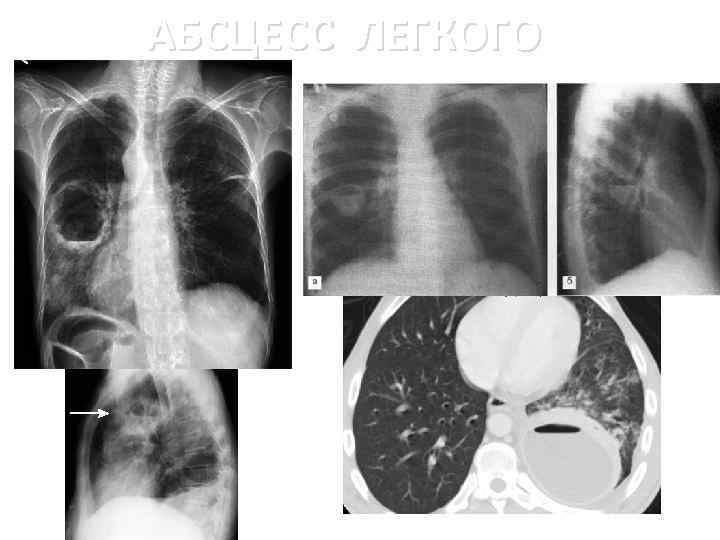

Медицинская тема: легочные осложнения при пневмонии